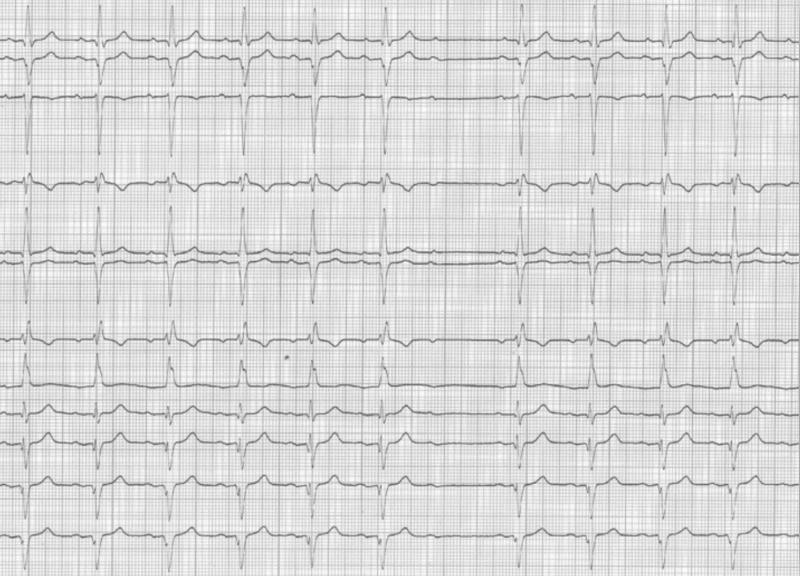

6.2.2 Le SCA non ST sus :

C’est un sous-décalage du ST, sans miroir ; Il correspond à la constitution non occlusive d’un thrombus sur une plaque d’athérôme rompue. Le territoire du sus décalage correspond à l’artère coupable.

Attention dans le cas d’un sous décalage circonférentiel avec sus décalage du ST il s’agit d’une souffrance du tronc commun qui est gravissime.

Fig 41 : Sous décalage de ST en antérieur. Pas de miroir. C’est un SCA non ST sus.

++++++++++++++++++++++++++++

Fig 42 : Sous décalage circonférentiel du ST avec sus ST en aVR. Il s’agit d’une souffrance du tronc commun, en amont de la bifurcation interventriculaire antérieure et circonflexe. Le territoire en souffrance est très vaste. C’est une situation critique.